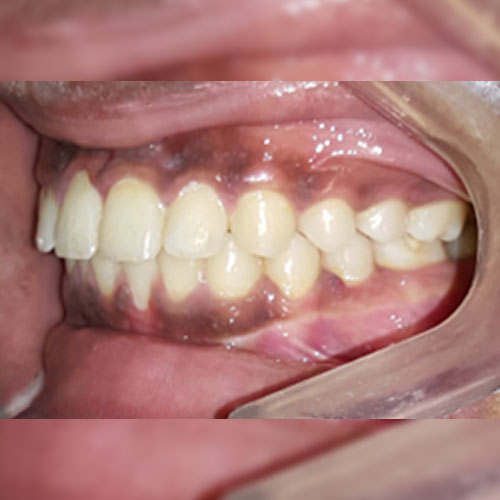

Smile Transformations

Real Patient Smile Transformations